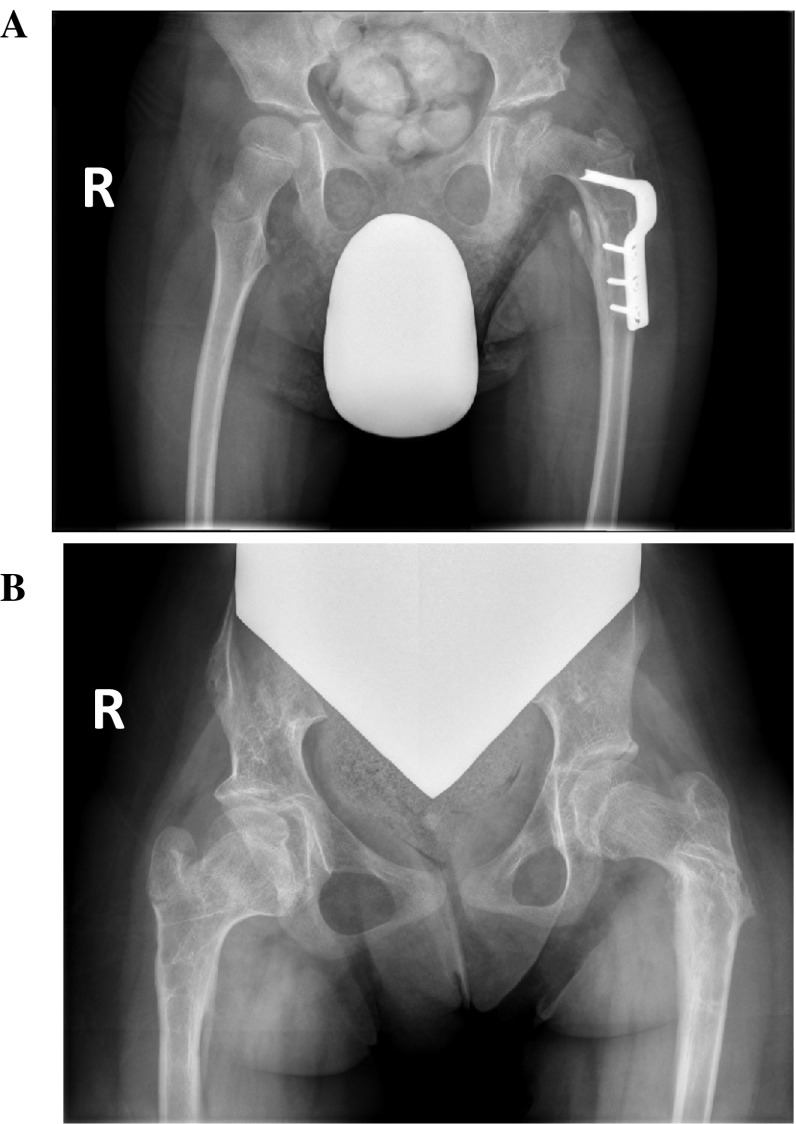

To quantify how many hips in total had AVN, those in which at least two surgeons identified AVN were considered positive. In trial one, 23 hips (18 %; 10 right, 13 left) were identified as having AVN, while in trial two, 21 hips (16 %; 8 right, 13 left) were identified. Of the right hips, seven were identified in both trials, with three and one hips independently identified in trials one and two, respectively. Of the left hips, 11 were identified in both trials with two hips independently identified in each. Between the two trials, a total of 11 right hips and 15 left hips in 25 different patients were diagnosed with AVN (Table 1). There were eight hips in which all four surgeons positively identified AVN, and eight hips in which only two surgeons identified AVN. Example radiographs of these optimal and suboptimal agreements are shown in Fig. 1a, b, respectively. In comparison, there were 81 hips (41 right, 40 left) in which all four surgeons reported no AVN in either trial.

Fig. 1.

Optimal and suboptimal agreement between pediatric orthopaedic surgeons on the presence of avascular necrosis (AVN) of the femoral head in children with cerebral palsy. Anteroposterior radiographs of the hips were identified to have AVN by a 4/4 surgeons (left hip), and b 2/4 surgeons (right hip)